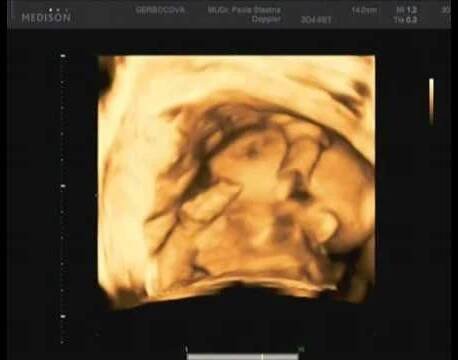

3D sonografia / 3D ultrazvuk - Druhý trimester - Srdce

3D ultrazvuk je lékařská ultrazvuková technologie, často používaný v porodnické ultrasonografii (během těhotenství), poskytující troj-dimenzionální obrázek plodu. Wikipedie